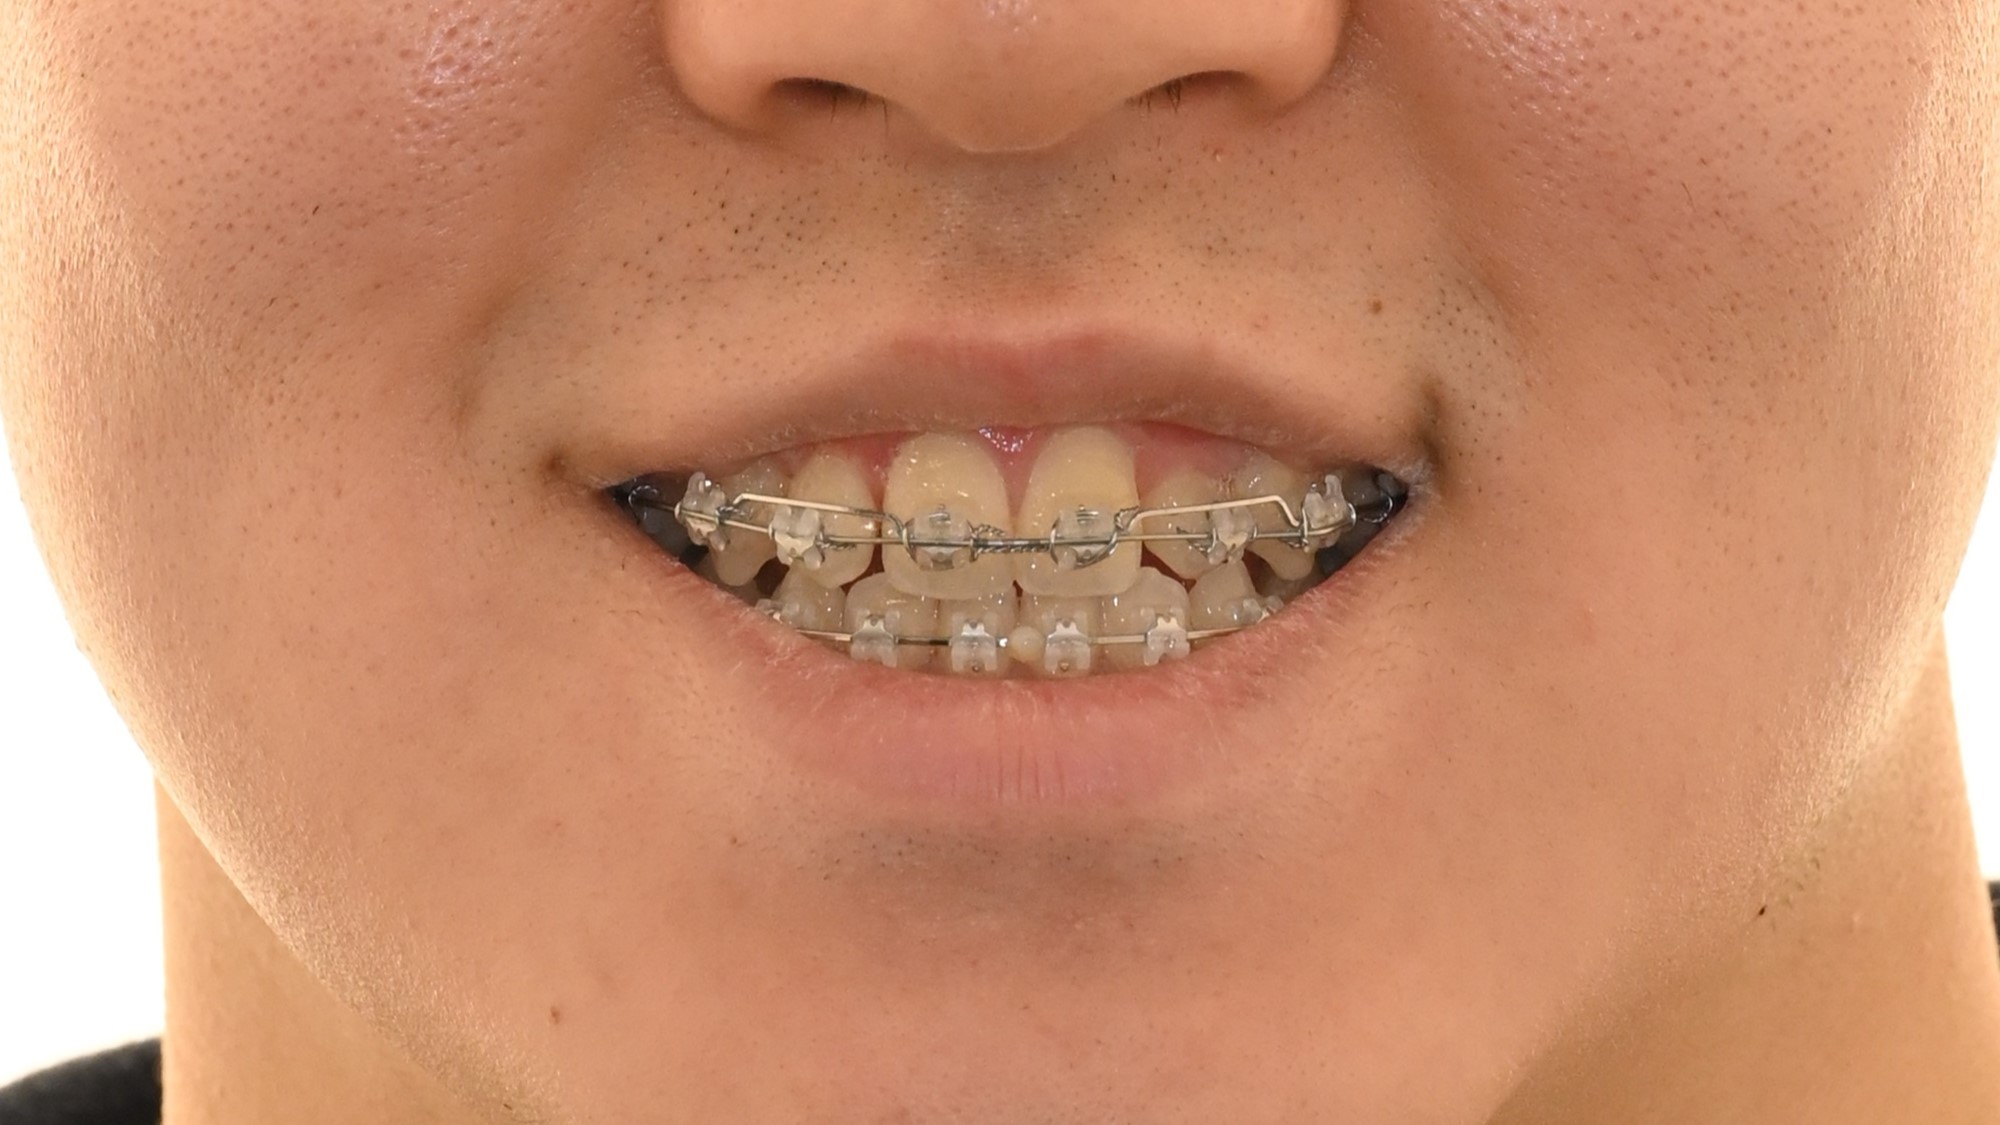

위 예시 사진을 보면 전후방적으로 위턱에 비해 아래턱이 큰 모습이죠?

바로, 전후방적으로 위턱에 비해 아래턱이 큰 골격적 특징 때문입니다.

가장 눈에 띄는 문제는 위 앞니가 삐뚤빼뚤하며 위아래 측절치가 거꾸로 교합되는 앞니 반대교합이었습니다.

정상적인 교합에서는 위 앞니가 아래 앞니를 2-3mm 정도 덮어야 하는데, 이 환자분의 경우 위 앞니가 아래 앞니를 덮는 양이 현저히 부족했습니다.

구치부 관계에서도 양측 모두 3급 부정교합을 보였으며, 이는 전체적인 교합 관계의 부조화를 의미합니다.

특히 주목할 점은 골격에 대해 상악 치아는 전방으로, 하악 치아는 후방으로 기울어져 있다는 것입니다.

이는 부정교합을 보상(compensation)하려는 자연스러운 적응 과정에서 나타난 변화로, 실제 골격적 부조화가 치아 경사도에 의해 어느 정도 가려져 있음을 시사합니다.